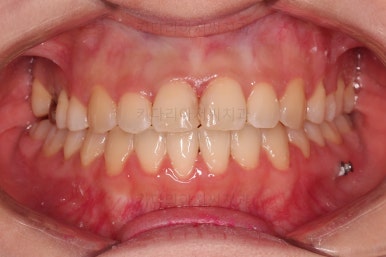

초진 시, 입안의 모습입니다.

아래 중앙선이 윗니의 정중선에 비해 우측으로 많이 쏠려있고요.

전반적으로 아래 치열이 우측으로 가 있어서 특히 송곳니 부분에서의 반대교합이 두드러졌어요.

(아래 송곳니가 위 송곳니보다 밖에 나와있는 상태)